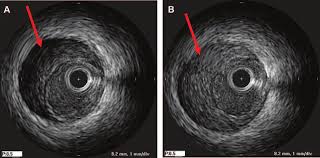

Ultrasonografia intravasculară (IVUS)

Reprezintă o investigație imagistică ce presupune explorarea spațiului vascular intracoronarian prin introducerea unei sonde la nivel arterial, care emite ultrasunete și captează reflexia țesuturilor.

Linia galbenă –lumenul vascular;

Linia albastră – membrana externă elastică;

Zona verde – placa aterosclerotică.